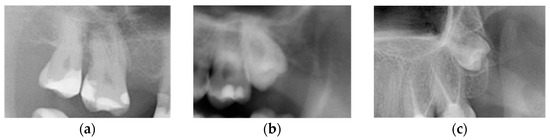

Additionally, M3s were categorized based on Winter’s classification in terms of their position in the dental arch relative to the long axis of M2s, according to the following criteria: (1) horizontal (angle between the long axes of an M2 and an M3 between 80° and 100°), (2) mesioangular (from 10° to 80°), (3) vertical (from −10° to 10°), and (4) distoangular (from −10° to −80°) (Figure 3) [23].

Figure 3. Third molar angulation: (a) horizontal, (b) mesioangular, (c) vertical, and (d) distoangular.